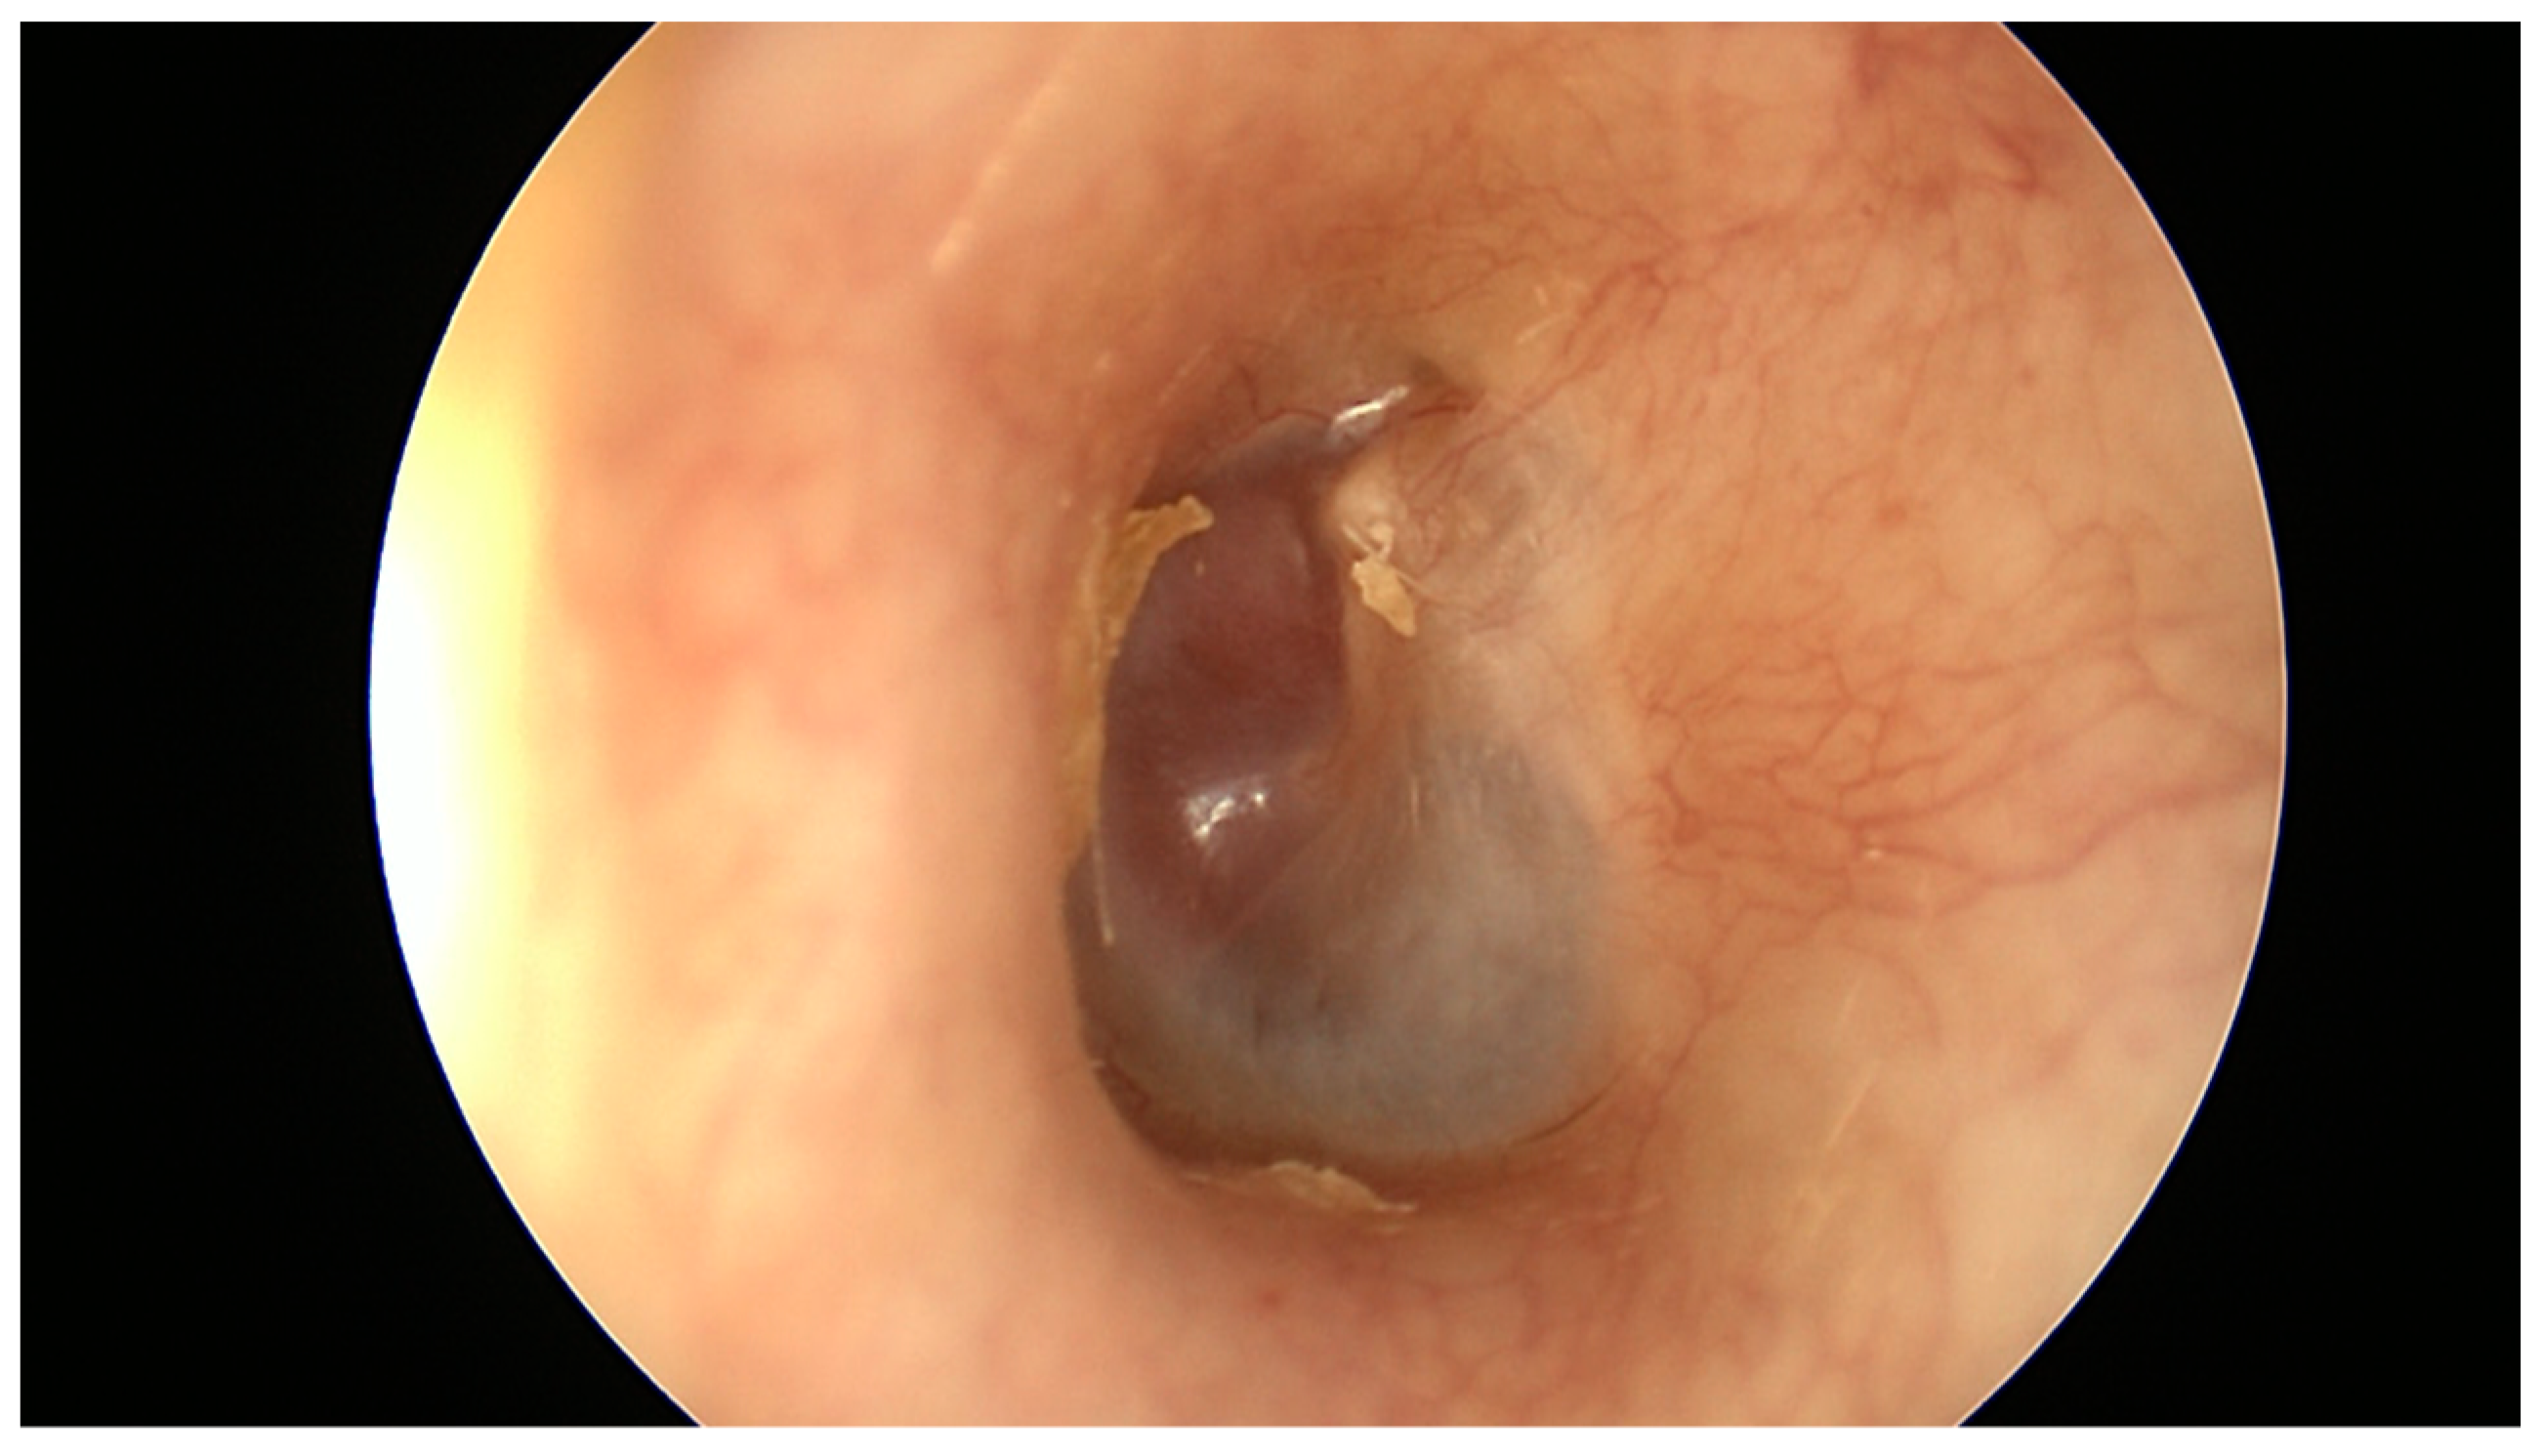

| A1 | Tumors completely visible on otoscopic examination |

| A2 | Tumor margins are not visible on otoscopy. Tumor may extend anteriorly to the Eustachian tube and/or to the posterior mesotympanum |